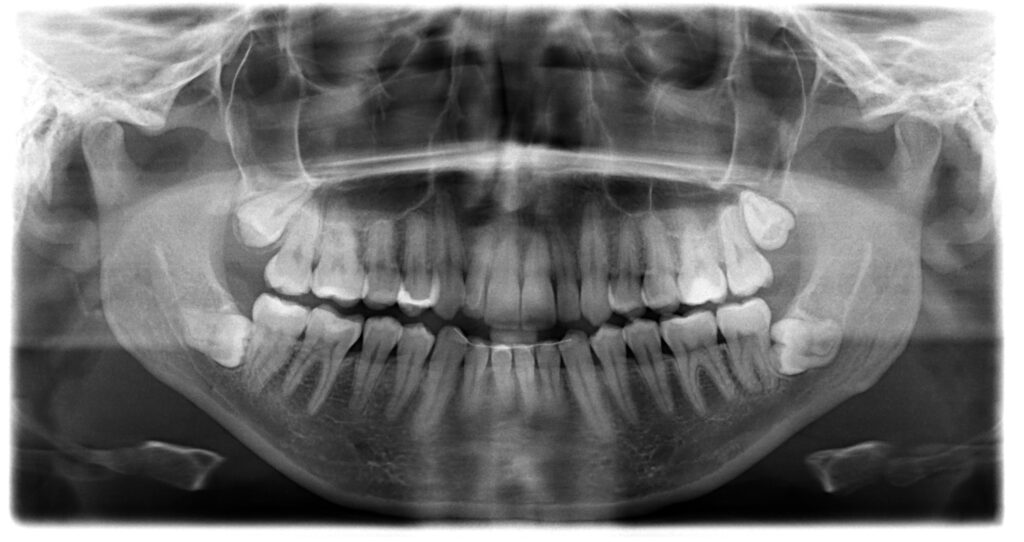

Wisdom teeth, or third molars, typically emerge between ages 17 and 25 and often lack sufficient room to develop properly. For adults over 50 considering clear aligner treatment, the position and condition of these teeth become important factors in planning your orthodontic care.

Not everyone needs wisdom teeth removed before starting treatment, but certain circumstances make extraction advisable. Impacted or misaligned wisdom teeth can potentially disrupt the careful tooth movements Invisalign creates. These molars may push against neighboring teeth, causing crowding that works against your alignment goals. Approximately 10 million wisdom teeth are extracted annually in the United States, with many removals performed to prevent future orthodontic complications.

However, if your wisdom teeth have erupted normally, sit in proper alignment, and cause no discomfort or crowding, removal may not be necessary. Your orthodontist can evaluate whether they pose any risk to your treatment success through digital imaging and clinical examination.

Wisdom teeth that remain trapped beneath the gum line or grow at awkward angles require attention before beginning aligner therapy. These impacted teeth can cause several problems that interfere with orthodontic treatment.

They may put pressure on adjacent molars, gradually shifting teeth out of alignment as your clear aligners work to move them into their proper positions. Partially erupted wisdom teeth also present hygiene challenges. Food particles and bacteria accumulate around these teeth, increasing infection risk during orthodontic treatment when maintaining excellent oral health becomes even more critical.